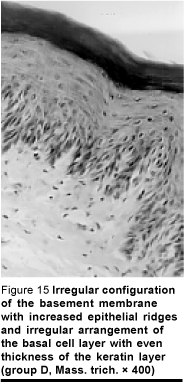

Group D. Increased epithelial thickness was noticed with a marked increase of clear cells reaching the granular cell layer. The keratin layer appeared homogeneous with increased thickness (Figure 13). Early keratinization was evident near the prickle cell layer which obscured the granular layer (Figure 14). As a result of the increased mitotic figures at the basal cell layer, irregular configuration of the basement membrane with lateral extensions of the epithelial ridges gave rise to the drop-shaped appearance seen (Figures 14 and 15).

The increased mitotic figures in the basal and suprabasal layers, resulting in the drop-shaped appearance of the epithelial ridges with lateral extensions, may be considered a reflex reaction of the epithelium to compensate for the missing superficial layer of keratin due to light exposure; it could be considered as a defence mechanism of the epithelium to protect the underlying connective tissue.